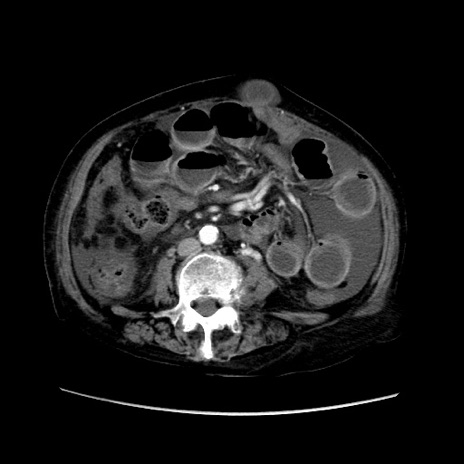

症例31(横断像)

【症例】80歳代 女性

【主訴】腹部膨満感

【現病歴】他院にて肝硬変にてフォロー中。1週間前から便秘、腹部膨満感、臍部腫瘤あり受診となる。

【既往歴】肝硬変

【身体所見】腹部膨隆あり、皮膚変化なし、疼痛なし。

【データ】WBC 4600、CRP 0.25